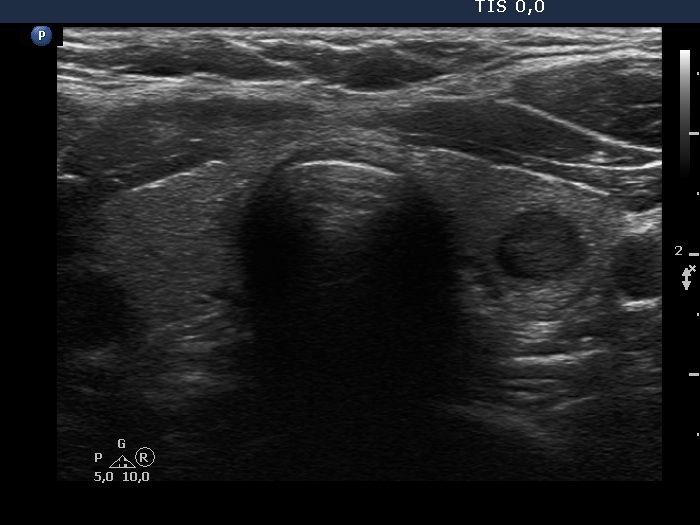

A conglomerate of lymph nodes was found 2 cm above the left lobe. The nodes did not have hilum but contained microcalcifications and presented irregular vascular pattern. (This was not noticed on the previous ultrasound examination.)

Cytology performed from the heterogeneous lesion and from the lymph node resulted in papillary cancer and metastasis of papillary cancer, respectively.